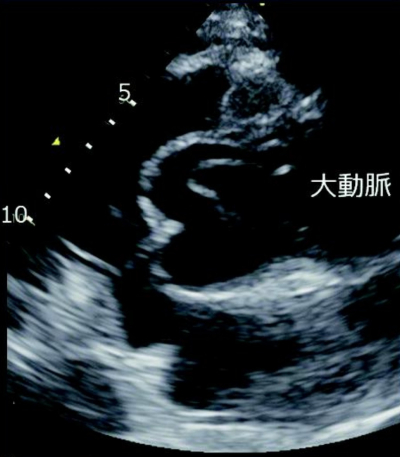

血液所見:赤血球 350 万、Hb 11.6 g/dL、Ht 39 %、白血球 9,600、血小板 21 万。血液生化学所見:AST 30 U/L、ALT 26 U/L、尿素窒 素 14 mg/dL、クレアチニン 0.6 mg/dL、血糖 99 mg/dL、Na 136 mEq/L、K3.8 mEq/L、Cl 100 mEq/L。心電図では明らかな ST-T 変化は認めない。胸部エックス線写真及び心エコー図を別に示す。